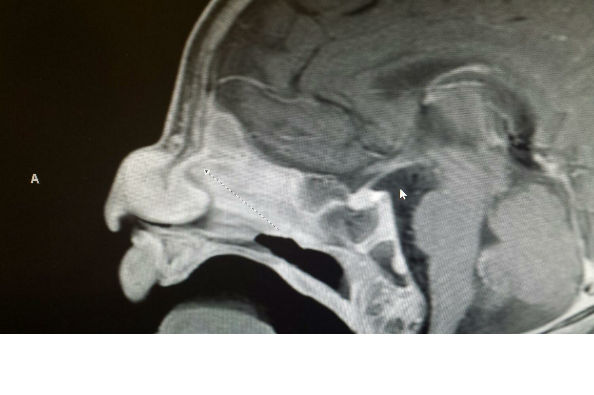

At 1 week old Jaxson had his first appointment with the Otolaryngologist. After a 5 minute examination the doctor had more troublesome news. He let my sister and Joel (Jaxson's father) know that he had a sneaky suspicion the mass was growing into Jaxson's brain. He wanted Jaxson to have an MRI and CAT Scan within the next 7 days.

August 5th came. Finally answers, but the MRI and CAT Scans came with serious risks of their own. Jaxson was only 6 weeks old and had to be put under anesthesia. The risks that came with the anesthesia was enough to give any mother and father anxiety attacks. When the scans were finally done, they were atlas able to return back to the room with little Jaxson. Everything had gone well and he was ready to eat. They waited in the recovery room thinking that the worst was almost over. They just needed the Otolaryngologist to come into the room and confirm that the mass was just a cyst and that he could easily remove it through Jaxson's nostril. They were not at all prepared for the news they were about to receive...

The Otolaryngologist brought the images up on his computer and as he was explaining to my sister and Joel, what the MRI and CAT Scans revealed, my sisters legs became weak and her arms became heavy. She couldn't stand anymore. The nurses rushed over with a chair for her to sit down. She couldn't even hear what they were trying to say to her anymore. She felt like she couldn't breathe.

The news was the worst news that could have been given, confirmed. The mass was a tumor with an extension attaching to his brain. It was called a Glioma Tumor. Glioma Tumors are made up of glial cells, which are supportive cells that help the brain cells function.

On September 25th the Neurosurgeon delivered good news and more bad news. The bad news was that Jaxson's tumor is extremely rare in the fact that it grew through his sinus cavity. There have only been 1 or 2 reported cases in the whole Northwestern Hemisphere. The good news was that although she has never seen this type of tumor, she had scrubbed in on a few that had grown from the base of the neck while interning. She was very confident about the procedure (bi-frontal craniotomy & resection of nasal glioma with intracranial extensions) and her ability to remove the tumor successfully. She did however add one more risk factor to the surgery. She said that the hardest part of the surgery she is performing, is insuring that no brain fluid is leaked while she is removing the tumor.

At 1 week old Jaxson had his first appointment with the Otolaryngologist. After a 5 minute examination the doctor had more troublesome news. He let my sister and Joel (Jaxson's father) know that he had a sneaky suspicion the mass was growing into Jaxson's brain. He wanted Jaxson to have an MRI and CAT Scan within the next 7 days.

August 5th came. Finally answers, but the MRI and CAT Scans came with serious risks of their own. Jaxson was only 6 weeks old and had to be put under anesthesia. The risks that came with the anesthesia was enough to give any mother and father anxiety attacks. When the scans were finally done, they were atlas able to return back to the room with little Jaxson. Everything had gone well and he was ready to eat. They waited in the recovery room thinking that the worst was almost over. They just needed the Otolaryngologist to come into the room and confirm that the mass was just a cyst and that he could easily remove it through Jaxson's nostril. They were not at all prepared for the news they were about to receive...

The Otolaryngologist brought the images up on his computer and as he was explaining to my sister and Joel, what the MRI and CAT Scans revealed, my sisters legs became weak and her arms became heavy. She couldn't stand anymore. The nurses rushed over with a chair for her to sit down. She couldn't even hear what they were trying to say to her anymore. She felt like she couldn't breathe.

The news was the worst news that could have been given, confirmed. The mass was a tumor with an extension attaching to his brain. It was called a Glioma Tumor. Glioma Tumors are made up of glial cells, which are supportive cells that help the brain cells function.

On September 25th the Neurosurgeon delivered good news and more bad news. The bad news was that Jaxson's tumor is extremely rare in the fact that it grew through his sinus cavity. There have only been 1 or 2 reported cases in the whole Northwestern Hemisphere. The good news was that although she has never seen this type of tumor, she had scrubbed in on a few that had grown from the base of the neck while interning. She was very confident about the procedure (bi-frontal craniotomy & resection of nasal glioma with intracranial extensions) and her ability to remove the tumor successfully. She did however add one more risk factor to the surgery. She said that the hardest part of the surgery she is performing, is insuring that no brain fluid is leaked while she is removing the tumor.